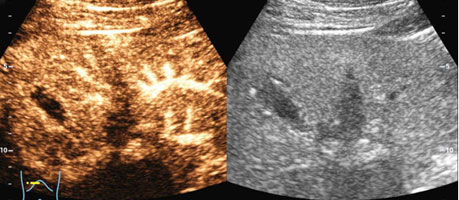

在超声造影检查前,二维超声检查可见患者肝左内叶胆囊旁低回声结节,大小为2.0cm×1.1cm,形态稍欠规则,边界清,结节内部未见明显血流。经患者左侧肘部静脉注入超声造影剂后,发现肝内结节与周围肝实质三期同步增强,考虑结节为良性病变,肝内结节是由于肝内脂肪沉积不均所致。检查过程持续10 分钟,造影结束后留观 15 分钟,患者无不良反应后拔出静脉穿刺针,检查结束。得知自己肝内结节考虑是良性病变,只需定期复查时,压在王先生心里的一块大石头终于落地了。

肝内新发片状低回声结节,二维图像上难以判断良恶性

通过造影剂,可实时动态观察结节内部的微循环血流灌注情况,做出诊断